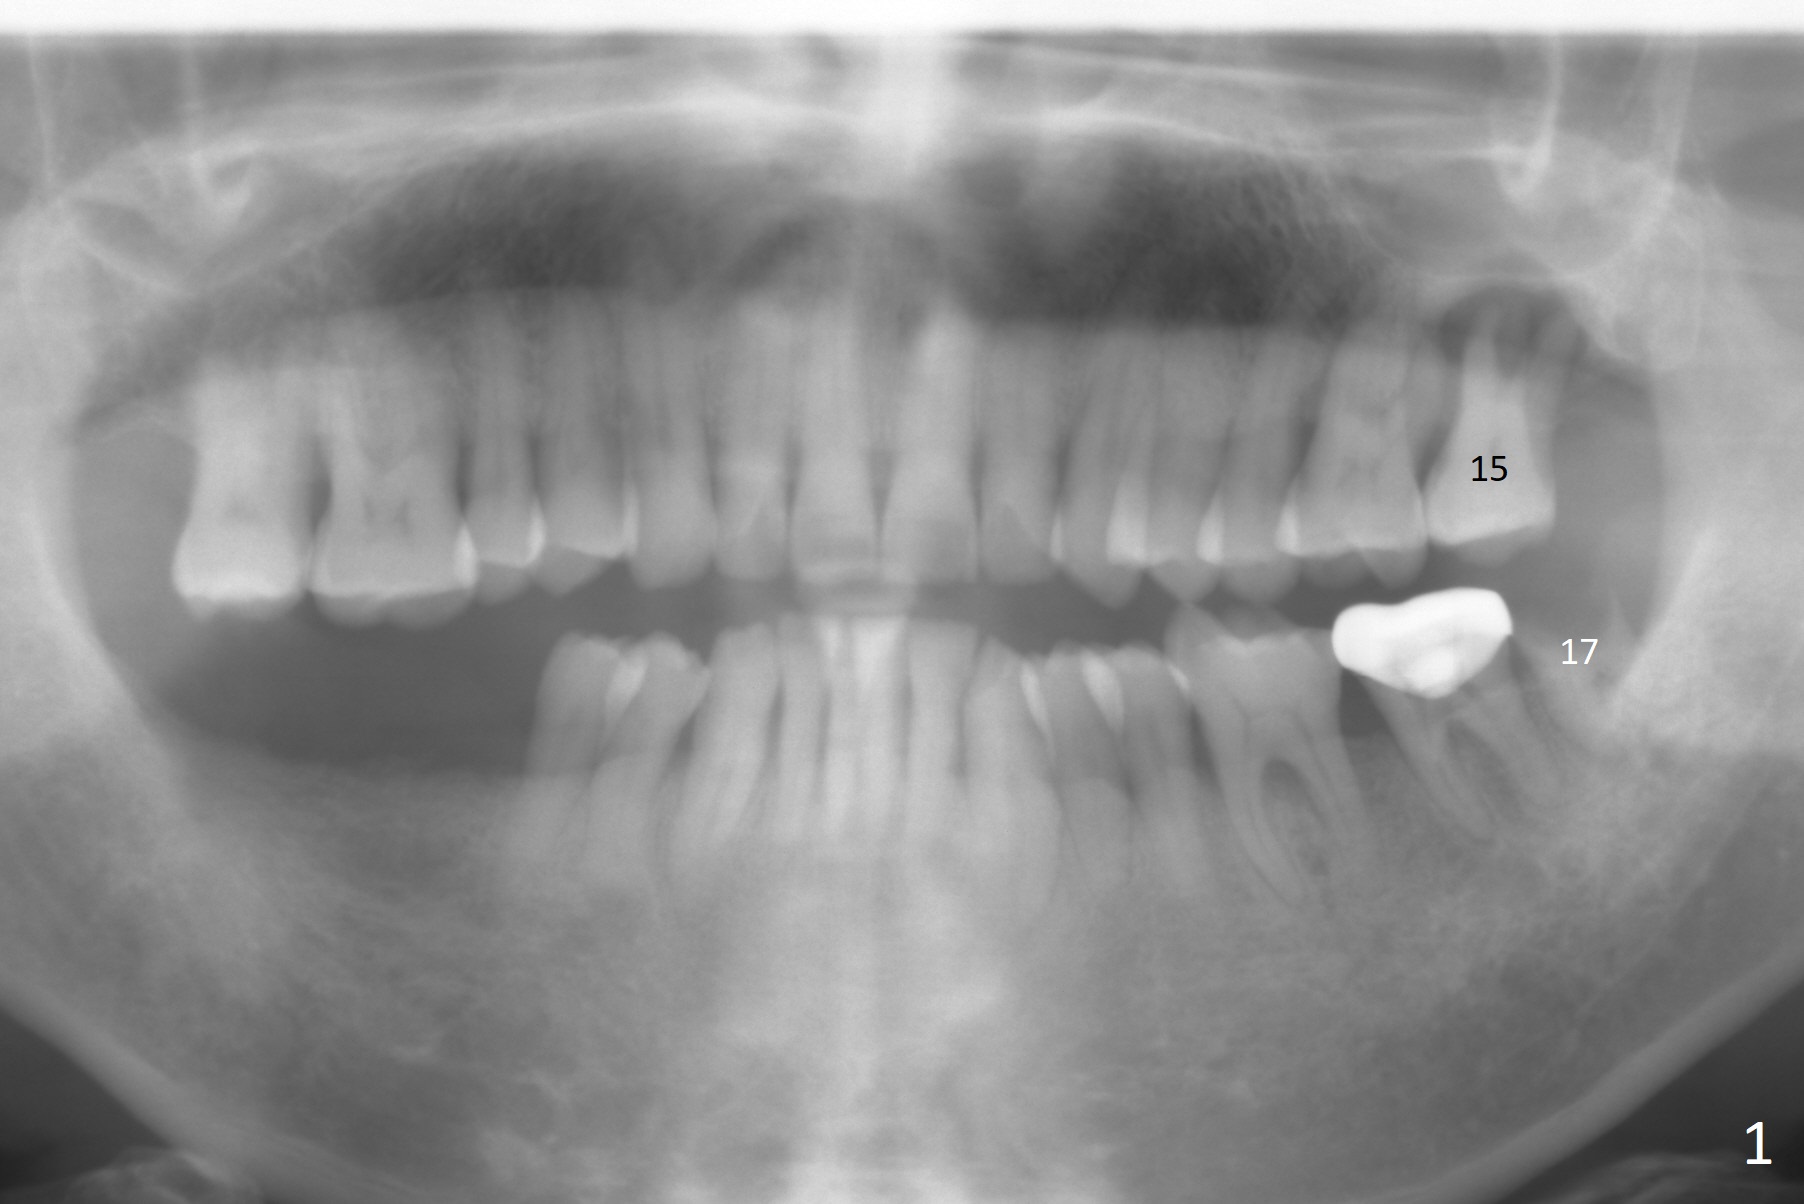

A 64-year-old man has poor dentition (Fig.1 (taken a year ago)). After extraction of #15 and 17 in China, the tooth #14 develops retrograde pulpitis with severe buccopalatal gingival recession (Fig.2). It appears that the septum is longer than the buccopalatal plates. A small and relatively long implant (3.8 or 4x11.5 mm) is placed within the boundary of the septum. The most peripheral socket is packed with PRF membranes (2-3 tubes) and collagen plug, while the portion close to the implant threads with Vera Graft. Please remember osteotomy depths with hard and soft tissue landmarks (Fig.2).